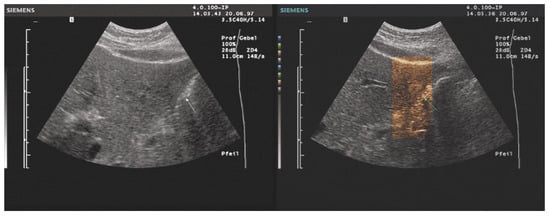

- Interventional Procedures: Enhanced tissue and needle visibility in color-tinted images improve safety and accuracy in ultrasound-guided interventions.

- The combination with speckle filters available in all high-end devices, similar to the low-pass filters used by Bleck et al. (1994) for tissue visualization [5], also yields significantly improved visualization results (Figure 5, Figure 6 and Figure 7). In principle, applications with new visualized texture analyses, such as random field models, are also conceivable [76,77].